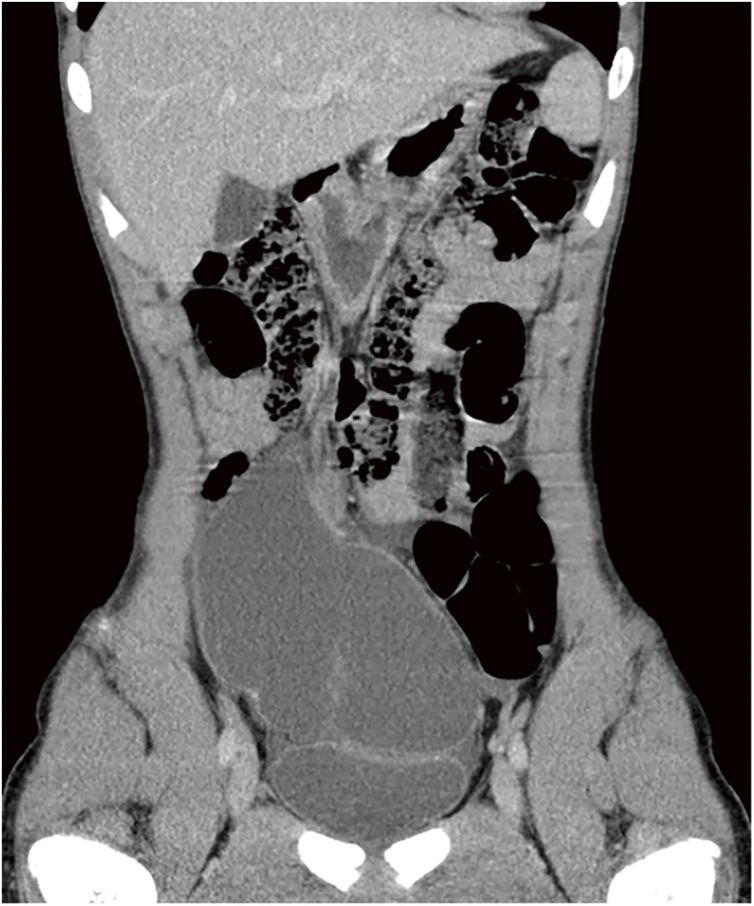

Case presentation: A 14-year-old boy was referred to our hospital for emergency surgery. Surgery revealed a primary tumor arising from the greater omentum. The tumor was macroscopically diagnosed as a benign omental lymphangioma and was resected en bloc with the greater omentum. A histopathological examination of the tumor revealed a simple columnar epithelium-like mesothelioma with poor cell-atypia. Immunohistochemical examination showed antibody reactivity in the cyst epithelium, including an anti-calretinin antibody. The final pathological diagnosis was a mesothelioma originating from the peritoneum.